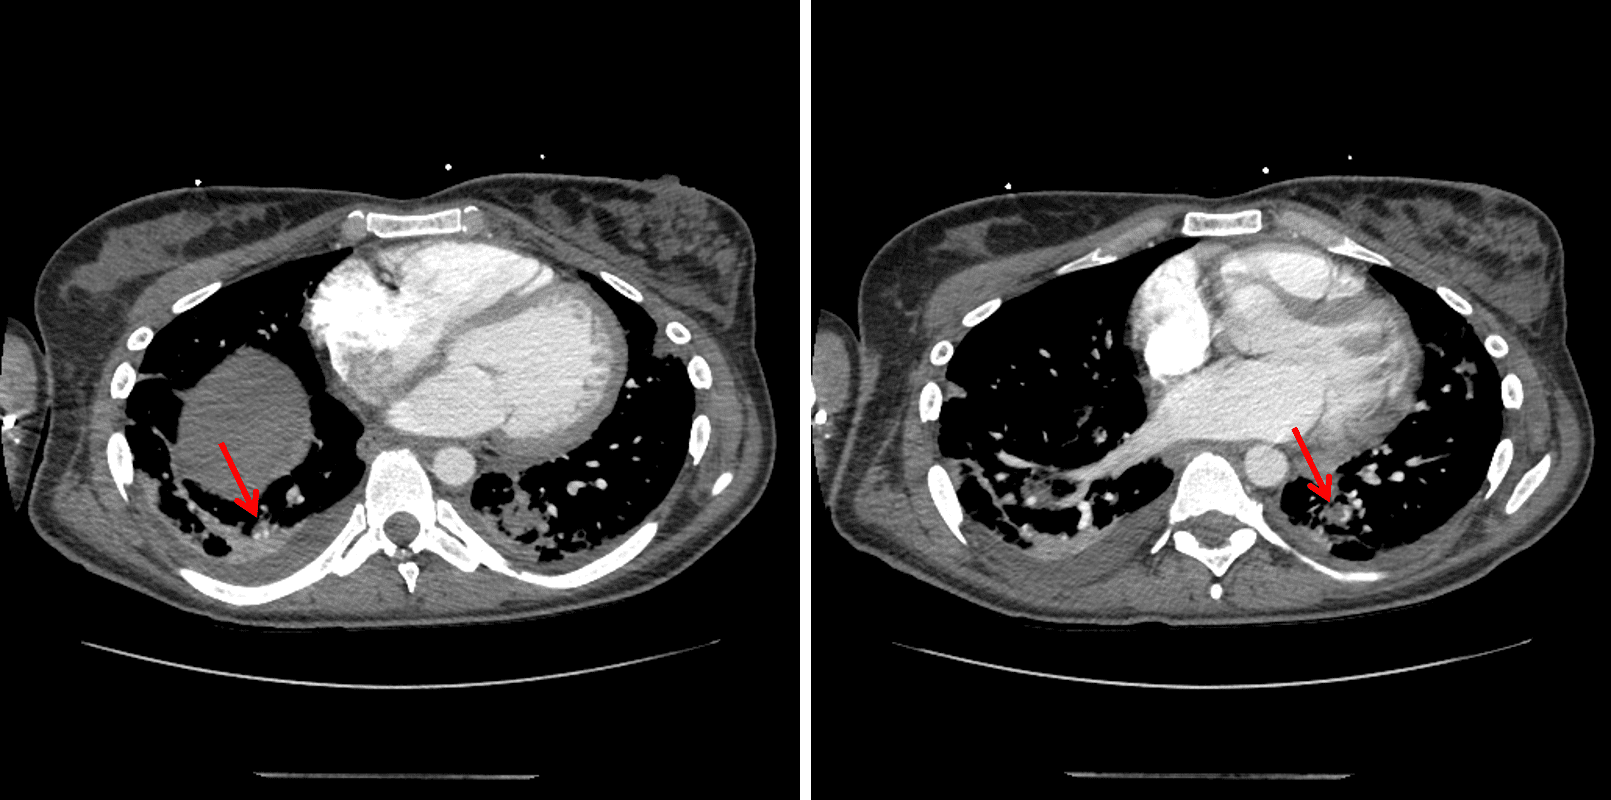

CT

Sample ReportAcute bilateral subsegmental pulmonary thromboembolism without CT evidence for right heart strain. In combination with the finding of scattered bilateral peripheral cavitary pulmonary nodules, this raises concern for septic embolic disease.

Mild dependent atelectasis and trace bilateral pleural effusions.